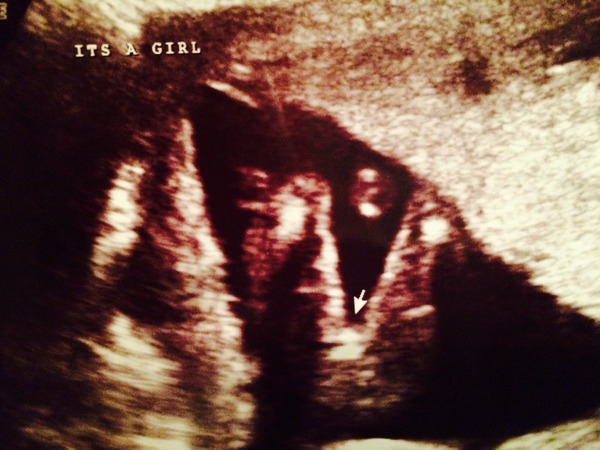

Siarie · 10/11/2014 19:13

Well it's pink ladies! So I won't be adding to the boy stats after all!

Congrats Siarie, that's what you wanted isn't it? Smile

Siarie · 10/11/2014 20:27

Brixton yeah it's really welcomed news. Takes the stress off now for that girl that I wanted.